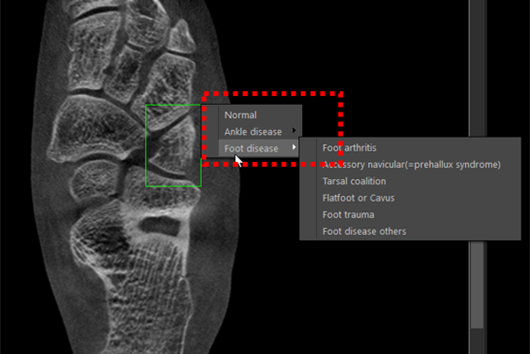

- AI 모델 3

- 질환 진단 보조를 위해 병변 위치를 추정할 병변 위치 데이터 기반 경계 박스 예측 모델 개발

- 병변 위치 데이터를 이용한 병변 위치 추정 모델 개발

- 거골 연골 병변, 무지외반증, 부주상골 증후군, 족근졸 유합 등의 병변 클래스와 이에 해당하는 경계박스를 예측하여 출력

- YOLO 기반 모델에 원본 이미지와 각 병변 클래스에 해당하는 위치가 레이블링 된 데이터(경계박스 좌표(x,y,w,h),)를 학습 데이터 셋으로 활용

- 빠른 속도와 안정적인 정확도를 보여, 다양한 도메인의 경계박스 추정 Task에서 많이 활용되는 YOLO 모델을 Baseline 모델로 선정